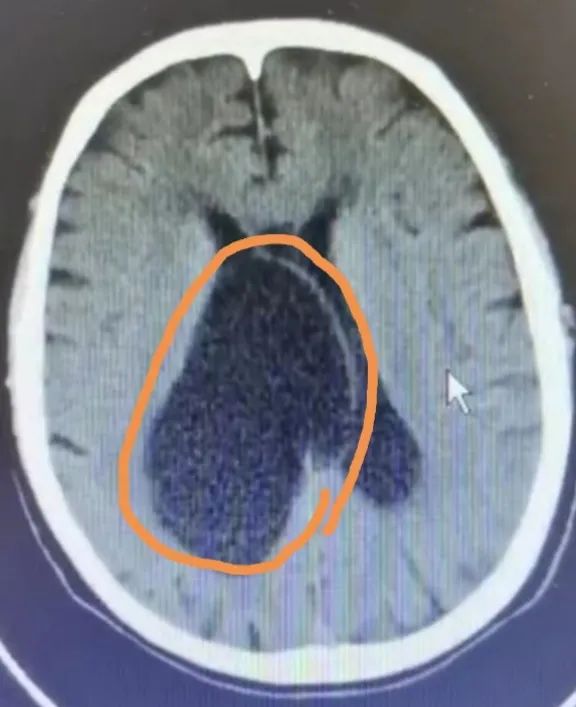

神经外科迅速为洛叔叔完善相关检查,CT显示右侧侧脑室囊性占位。

CT显示右侧侧脑室囊性占位